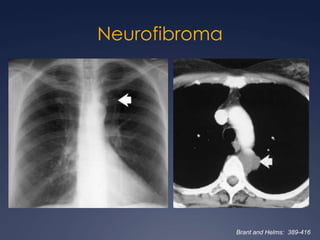

Patología mediastinal no vascularByanka Lorena Pozzo SalvatierraGrupo CT - Scanner